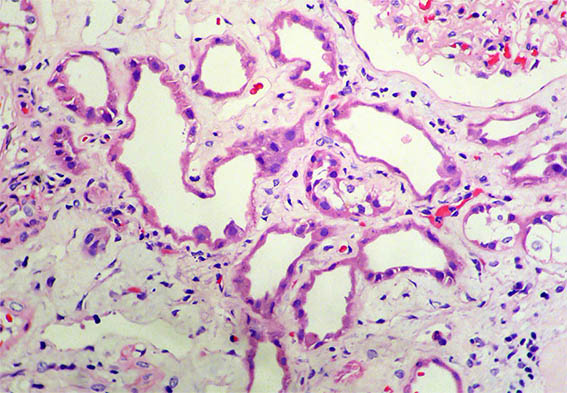

Figura 3.

H&E, X400.